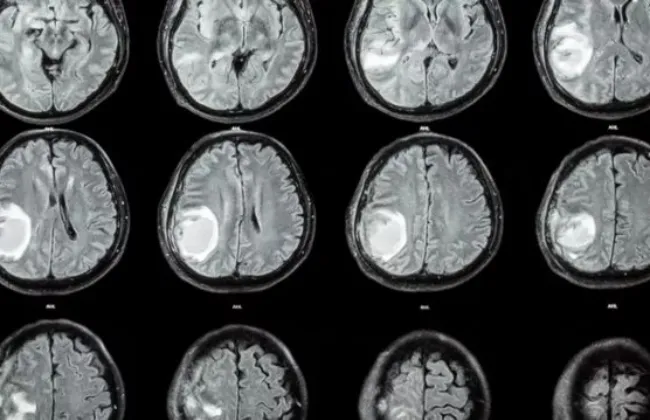

معلومات بسيطة تسعف مريض السكتة الدماغية

السكتة الدماغية هي ثاني أسباب الوفاة وثالث أسباب الإعاقة على مستوى العالم

ووفقاً لمنظمة الصحة العالمية، يُعاني نحو 15 مليون شخص من السكتة الدماغية سنوياً حول العالم

ويفقد 5 ملايين منهم حياتهم، في حين تتسبب بعجز دائم لعدد مماثل من المرضى، وتُشير الإحصائيات

أيضاً إلى أن شخصاً واحداً يُصاب بسكتة دماغية كل 40 ثانية في عالميا . هذه الأعباء تُشكل تحدياً كبيراً